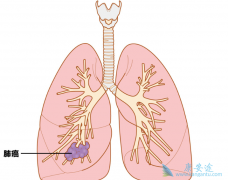

2013年间,在日本被诊断为肺癌的患者约11万人。男性患者约为女性患者的2倍。这是由于男性的吸烟率相对较高的原因。肺癌中和吸烟有因果关系的扁平上皮癌患者在男性患者中压倒性的居多,而女性的肺癌则是腺癌为多。从性别来看,男性的癌患者中,肺癌居第二 ...

肺癌是什么病? 肺癌的治疗 有作用吗?肋骨和横隔膜所包围的胸腔里,左右各有一个肺。左肺和右肺之间的空间被称作纵隔,心脏,大血管,气管和食道都在里面。肺的主要作用是,摄取氧气到体内,排出二氧化碳。口鼻吸入的空气进入气管,通过支气管进入左右的 ...